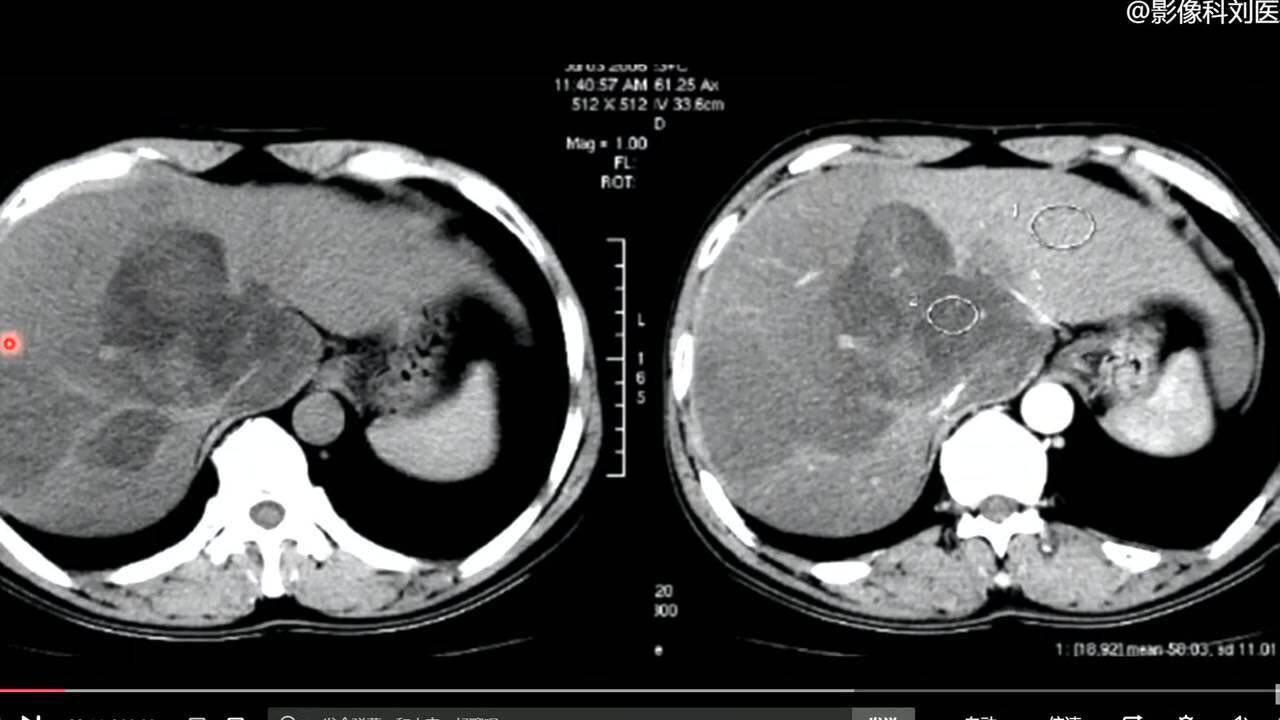

弥漫性脂肪肝伴正常肝岛一例ct增强病例

脂肪肝的ct诊断:肝脏密度减低,低于脾脏10hu以上,或肝脏密度低于40hu.